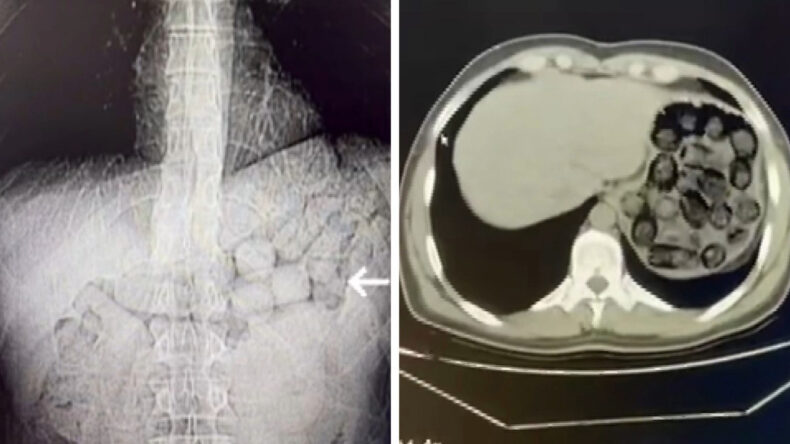

Şüphelilerin yutma tekniğiyle uyuşturucu madde taşıdığı belirlenince hastaneye sevk edilerek gerekli muayeneleri yapıldı.

Çekilen tomografi görüntülerinde, şüphelilerin mide ve bağırsak bölgelerinde yabancı cisimler tespit edildi.

Üç gün süren gözlemler sonucunda yapılan müdahaleyle, şüphelilerden 91 kapsül halinde toplamda 807,15 gram metamfetamin çıkarıldı.